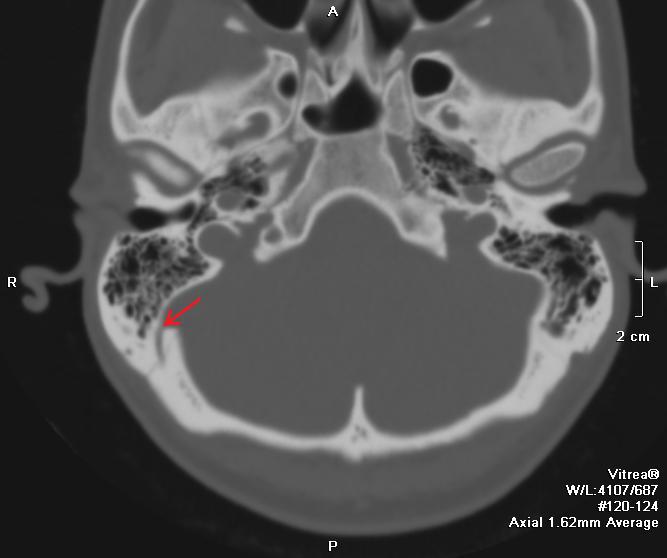

КТ анатомия сосцевидного отростка: особенности и показания